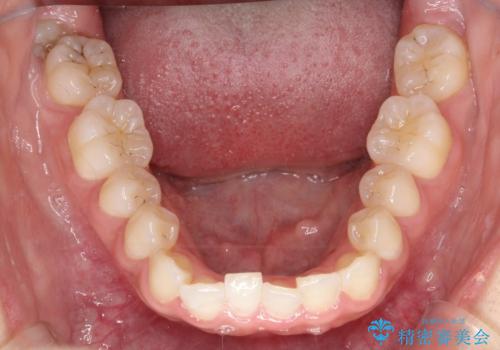

- 前歯の凸凹を主訴に来院された患者様です。

カウンセリング時に、側切歯が矮小歯であることを指摘したところ、適切な幅径での修復を希望されました。

インビザラインを用い、計画通りに歯並びを改善することができました。

矮小歯の幅径を大きくすることで、より理想的な噛み合わせを作ることができます。